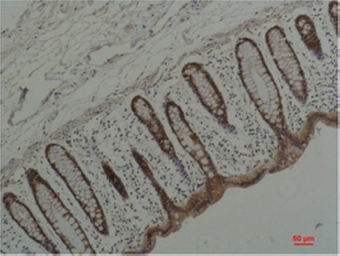

IHC-P analysis of human colon carcicnoma tissue using GTX33995 Hsp90 alpha antibody [1F6].

Dilution : 1:200